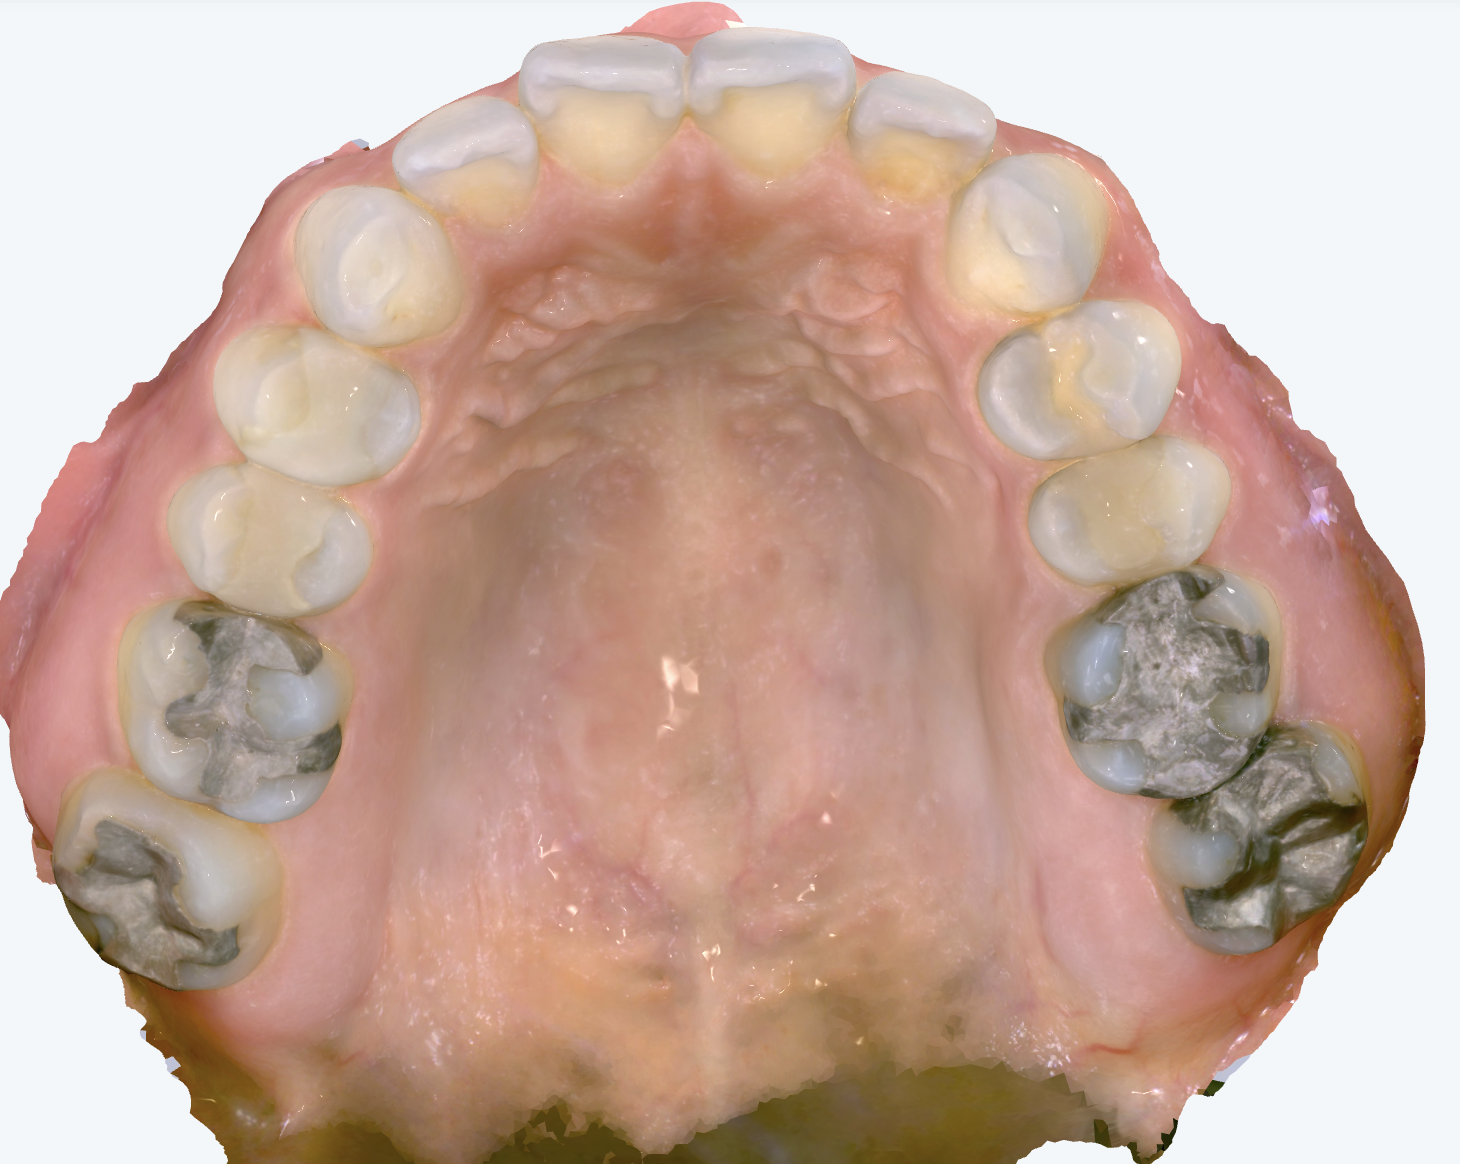

初診時の画像診断

奥歯の咬み合わせには、わずかに出っ歯の傾向がみられました。

上下の前歯が前方に位置しているため、口元が少し出た印象が見受けられました。